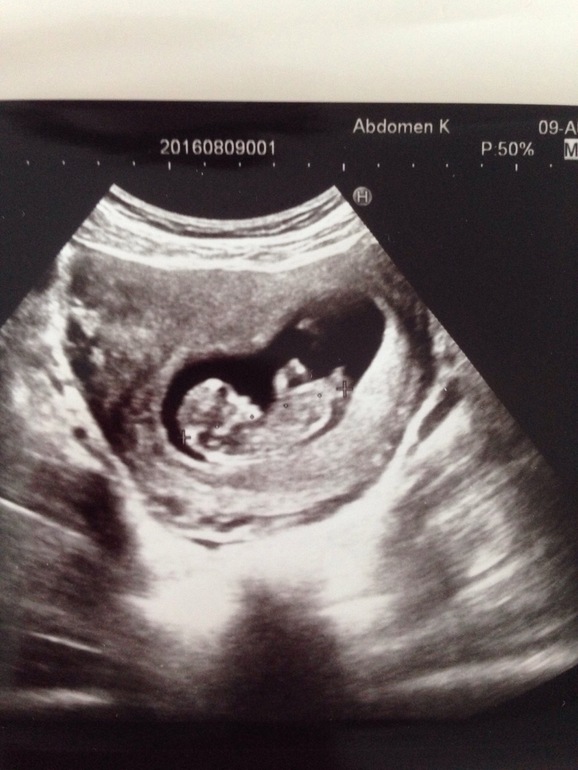

Наше узи в 11.4

УЗИ, КТГ, доплерСегодня, перед дорогой домой, сходила на узи, ну это образно говоря узи, мне было важно увидеть сердечко и что нет угроз, а то дорого предстоит длинная. Вообще делали минуту узи. Малыш 47.2 мм, сердечко 145 ударов. Какой же хороший человечек, ножками толкается, крутиться, а попочка какая пухлая😍😍😍 Теперь на скрининг ровно через неделю

Вот мы ттт шладенький мой малыш. А между ножек что-то торчит🙏🏻🙏🏻🙏🏻 Через недельку узнаем кто это

Здорово!! У меня у сына тоже в 12 недель что-то торчало, у дочки не торчало ))) и сердечко к сына было 145 , а у дочки больше ) Крепкого здоровья вам и малышу🙏🏻

Объясните, пожалуйста, торчит там, где крестик справа? Вижу фаберже, но крестик мешает)